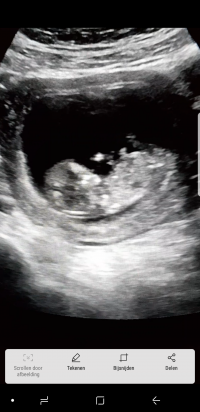

Bebegimin cinsiyeti?? Nub Teorisine göre nedir kızlar

10+5 yorum yapabilir misiniz rica etsem

Merhaba hanımlar. Yüklemiş olduğunuz görsellerin kalitesi iyi değil. Nub çıkıntısını göremedim. Bu nedenle bebeğinizin cinsiyeti hakkın da tahmin yürütemiyorum.